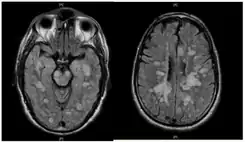

![]() La leucoencefalitis hemorrágica aguda fulminante muestra muchas lesiones. El paciente sobrevivió, pero permaneció en un estado vegetativo persistente | ||

La leucoencefalitis hemorrágica aguda produce múltiples lesiones inflamatorias en el cerebro y la médula espinal, particularmente en la materia blanca. Normalmente se encuentran en la materia blanca subcortical y central y en la unión gris-blanca cortical de ambos hemisferios cerebrales, cerebelo, tronco cerebral y médula espinal,[16] pero la materia blanca periventricular y la materia gris de la corteza, el tálamo y los ganglios basales también pueden estar implicados.